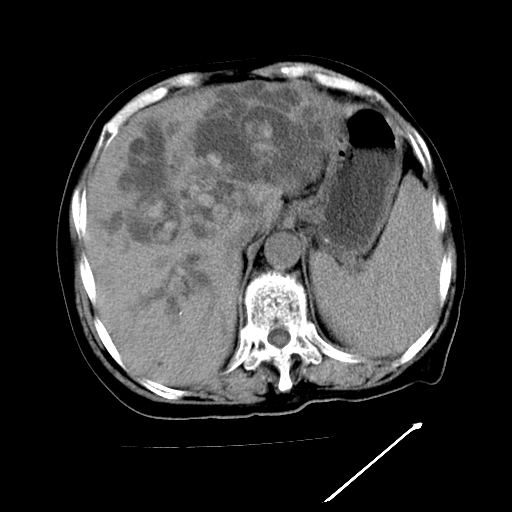

以下是引用卜一在2009-4-7 5:06:00的发言:[br]左右肝内胆管结石伴扩张合并胆系感染;不除外胆管细胞癌可能。支持! [br] [br]

以下是引用随光逐影在2009-4-7 8:21:00的发言:[br]肝内外胆管多发性结石并肝内外胆管扩张;胆系感染。